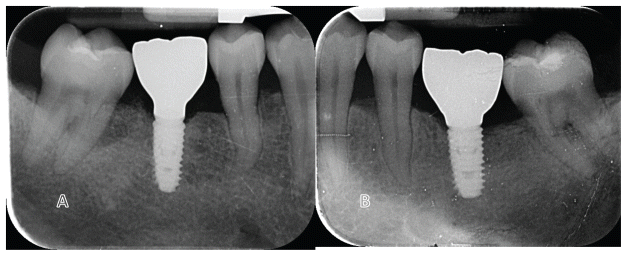

All surgeries were performed under local anesthesia with articaine hydrochloride and adrenaline 1:100,000 (Orabloc, Pierrel, Milan, Italy). After crestal incision and full-thickness flap elevation, implant sites were prepared either freehand or with the aid of a surgical guide. Manufacturer’s recommended protocols were followed (Osstem Implant). Bone quality was assessed subjectively. The first site was randomly assigned to receive either the KS (test) or TSIII (control) implants (Osstem Implant). Implants were placed at the crestal level or up to 2 mm subcrestally, based on anatomical conditions. Healing abutments were immediately connected if primary stability was ≥30–35 Ncm. On the contrary, cover screw would be place and second stage surgery planned. Flaps were closed with Vicryl 4.0 (or equivalent). Baseline periapical radiographs were taken with paralleling technique, for each study implant to prevent the risk of systematic error in performing periapical radiographs. Two to three months post-placement, either digital or conventional impressions were taken. Within one month, monolithic zirconia crowns bonded to titanium links were delivered after testing implant stability. Occlusal contacts were adjusted for light contact with the opposing dentition. Clinical photographs and radiographs were taken. Oral hygiene instructions were reinforced. Patients were enrolled in a maintenance program with six-month intervals. At each visit, professional oral hygiene sessions and clinical evaluations were performed, with particular attention to implant stability and occlusion. In addition, periapical radiographs were taken annually. According to the study protocol, patients were followed for research purposes for up to 5 years. Radiographs of both treatments are reported in figures 2–5. At each center, a single experienced clinician performed all surgical and prosthetic procedures, with optional assistance from a second clinician (e.g., a prosthodontist). All interventions and follow-ups were conducted at the respective sites using standardized materials and protocols to ensure consistency.

- Rate (expressed in mm) of peri-implant marginal bone level (MBL) changes were assessed on periapical radiographs took with the paralleling technique at implant placement, at initial loading, 6-month, 1,3 and 5 years after loading. In case of an unreadable radiograph, the radiograph has to be made again. Ideally digital radiographs should be taken, otherwise radiographs on conventional films will be scanned into TIFF format with a 600 dpi resolution, and stored in a personal computer. Peri-implant marginal bone levels were measured using the Scion Image (Scion Corporation, Frederick, MD, USA) software. The software was calibrated for every single image using the known distance of the first two consecutive threads. Measurements of the mesial and distal bone crest level adjacent to each implant were made to the nearest 0.01 mm. Reference points for the linear measurements were: the coronal margin of the implant collar and the most coronal point of bone-to-implant contact. Bone levels were measured at both mesial and distal sides and averaged. Bone levels were averaged at implant level and finally at group level.

No drop-outs were recorded. Overall, there were no failures of implants or prostheses, and no complications were encountered. Marginal bone levels (MBL) were evaluated at implant placement, crowns delivery and six month later. At implant placement, the mean MBL was 0.03±0.09 mm in the TS group and 0.04±0.13 mm in the KS group. At prosthesis delivery (3 months later), mean MBL was 0.32±0.27 mm in the TS group and 0.18±0.32 mm in the KS group. The marginal bone loss between baseline and prosthesis delivery was 0.26±0.24 mm in the TS group and 0.16±0.30 mm in the KS group. The difference between groups was statistically significant with lower value for KS group (0.10±0.23 mm; P=0.029). At the 6-month follow-up (9 months after implant placement), the mean MBL was 0.34±0.27 mm in the TS group and 0.21±0.32 mm in the KS group. The difference from baseline (implant placement) was 0.29±0.25 mm in the TS group and 0.19±0.30 mm in the KS group. The difference between groups was statistically significant with lower value for KS group (0.09±0.24 P=0.034). All the data are reported in table 2.